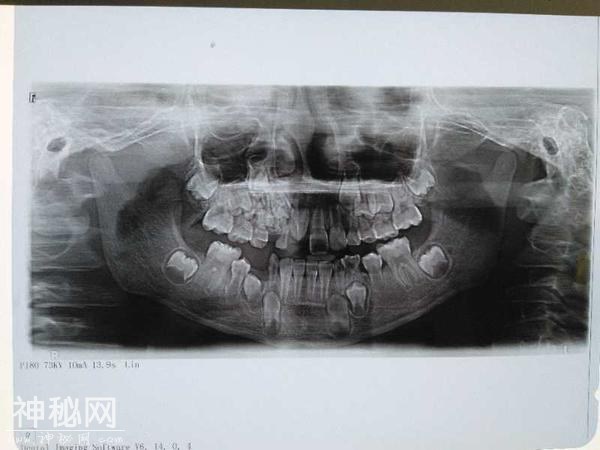

本报讯孩子到了换牙时期,牙齿没有萌出,大多数家长可能会不放在心上,认为早晚会换的。可是最近南阳一名9岁男孩因为门牙旁边的牙迟迟长不出来,家长带孩子到医院就诊,医生从孩子嘴里发现未萌出的牙组织周围竟然深藏了70多颗小牙!人怎么会长出这么多牙齿?这到底是什么怪病?

据了解,南阳市口腔医院口腔颌面外科主任蒋子超检查发现孩子的上颚部位有点鼓,根据患者口腔CT片发现有一2.0*2.0*2.0cm的高密度影,确诊该男孩患了牙瘤和上颌多生牙。牙齿也会得肿瘤?第一次听说这种怪病,这可吓坏了男孩的爸妈。在详细解释了男孩的病情并进行沟通后,家长同意医生为孩子实施手术。

6月27日上午,蒋子超主任在全麻下完整地摘除了男孩右上颌的组合性牙瘤,现场清点奇形怪状的小牙有70多颗。同时医生还拔除了该男孩口内的埋伏牙。